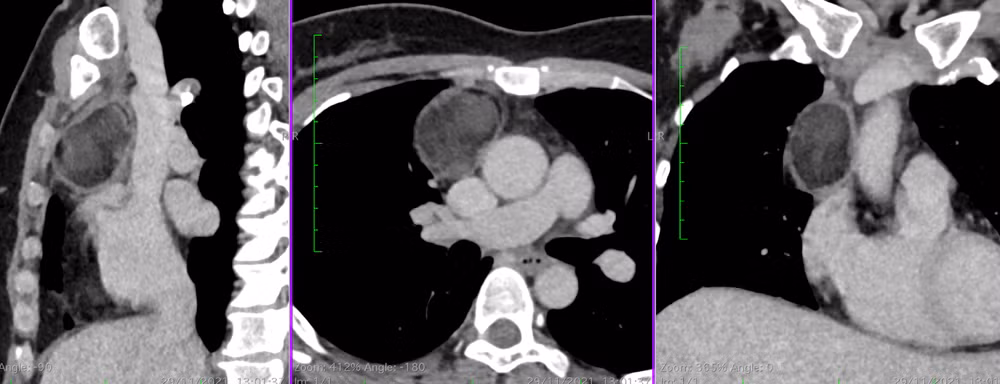

Hình ảnh khối “u quái” trên phim chụp CT phổi.

Khối u có đường kính hơn 5cm, bắt đầu chèn ép các tĩnh mạch chủ trên và động mạch chủ chung quanh. Nếu khối u tiếp tục phát triển sẽ cản trở máu từ tĩnh mạch chủ trên đi xuống, gây ra triệu chứng phù (hội chứng tĩnh mạch chủ trên). Vì thế, cần phẫu thuật ngay thời điểm này để loại bỏ hoàn toàn khối u quái, tránh những rủi ro sức khỏe sau này.

Là người trực tiếp thăm khám và điều trị cho bà Hoa, TS, BS Nguyễn Anh Dũng, Trưởng khoa Phẫu thuật Tim mạch-Lồng ngực, cho biết, khối u trung thất của bệnh nhân có cấu tạo rất lạ gồm cả lông, tóc, xương…, được gọi là “u quái”.